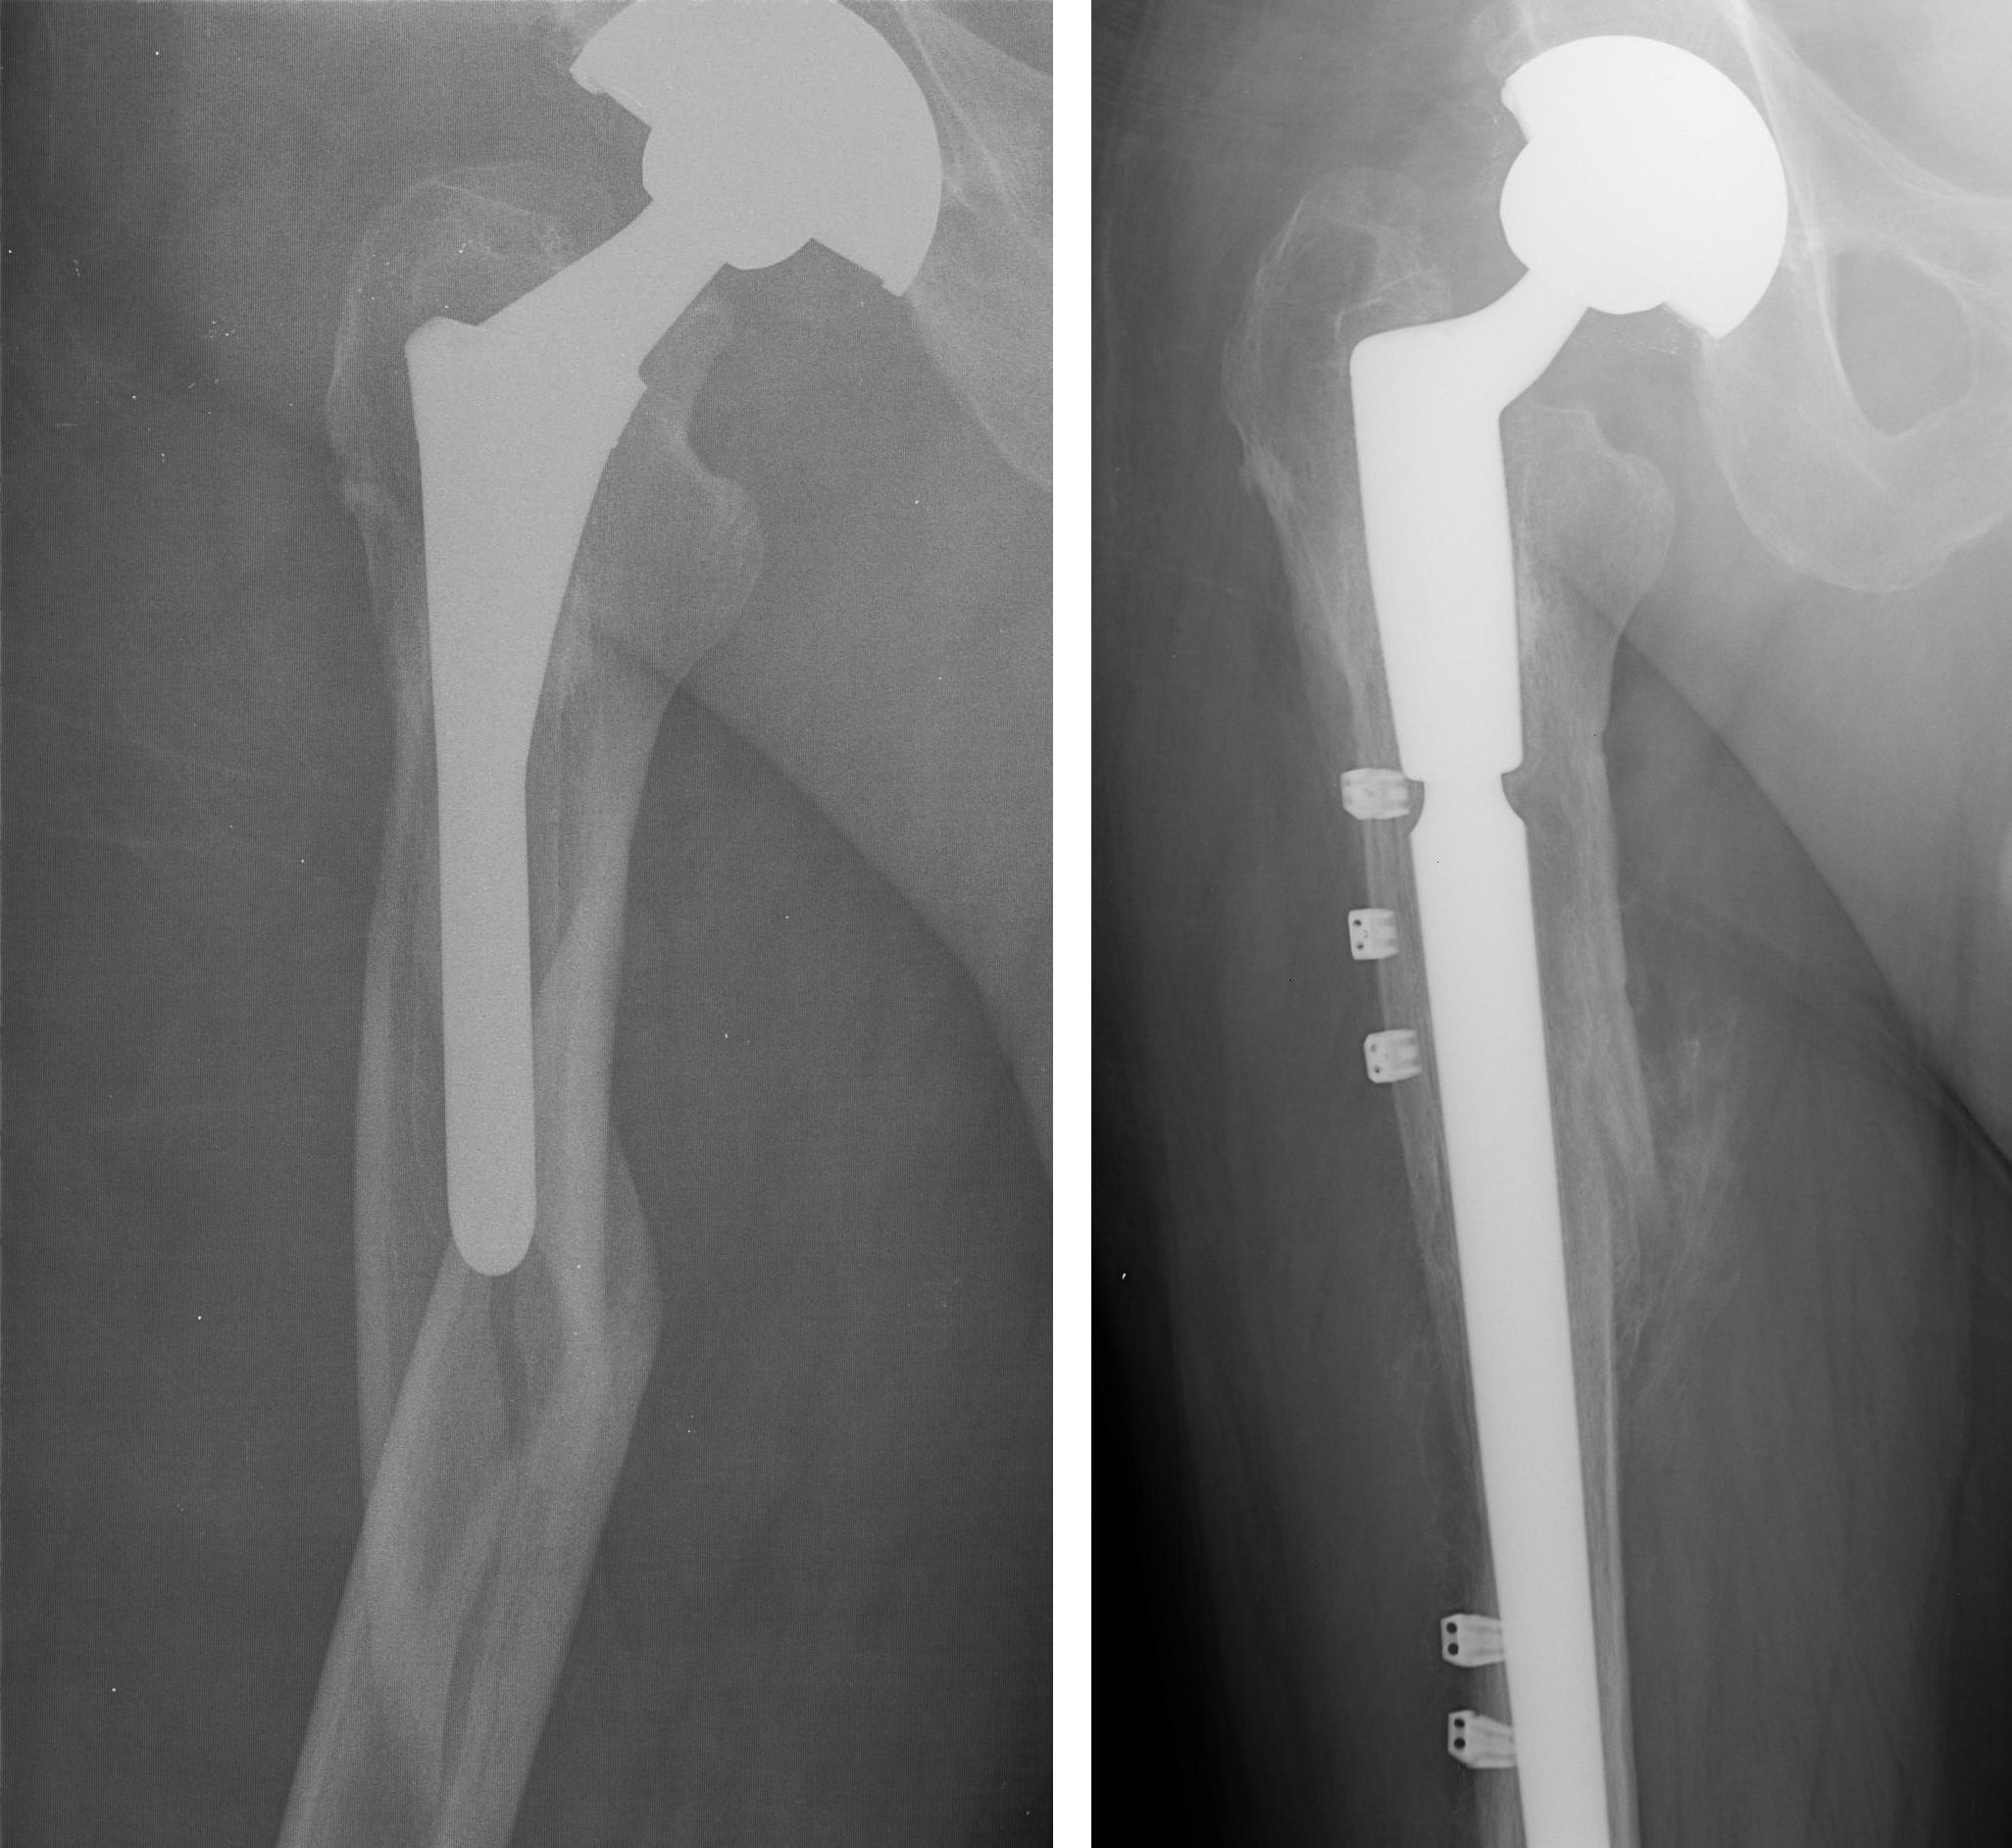

What helps with recovery. We performed a study to determine the prevalence severity and natural history of pain in the thigh in patients who had a total hip replacement with a porous-coated anatomic prosthesis and to determine if there was an association between the radiographic findings and the pain in the thigh. After undergoing total hip replacement surgery 2 years earlier a 65-year-old man comes to the office complaining of left thigh pain.

Fracture After Total Hip Replacement Orthoinfo Aaos

I Have A Patient With Start Up Thigh Pain 5 Years After Surgery And I Think The Femoral Component Is Loose How Can I Tell For Sure